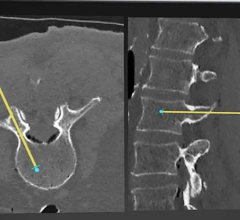

Computed tomography (CT) has long been a cornerstone of modern imaging, providing detailed 3D insights into the human ...